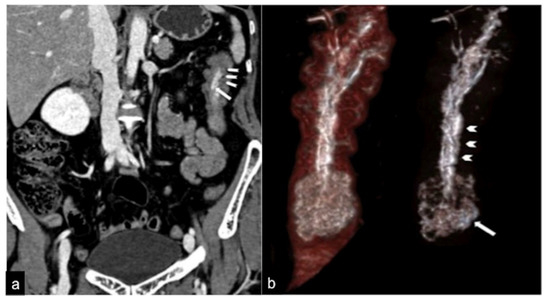

| Aorto-Enteric Fistula (Figure 31) | Bleeding in a patient with a history of surgery for aortic aneurysm. | A connection between the aorta and the intestinal lumen. Absence of adipose cleavage planes. |